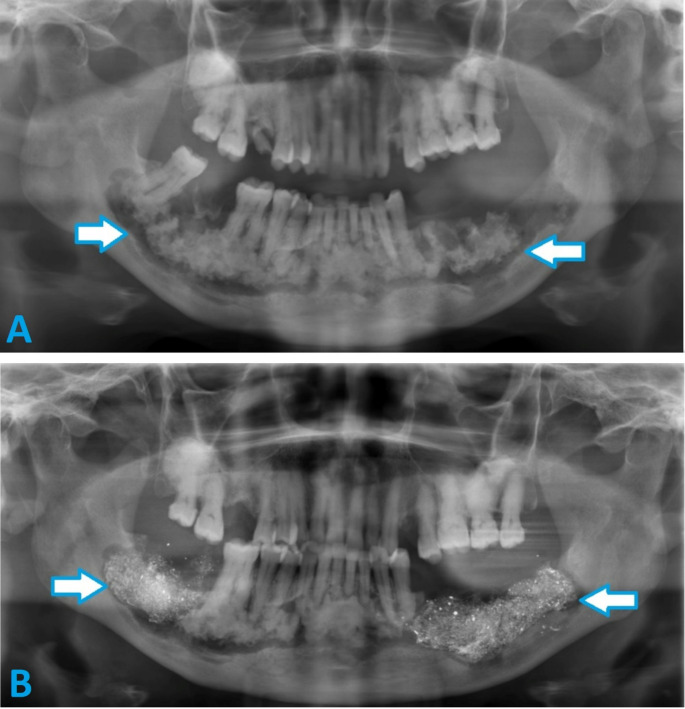

Abstract Image